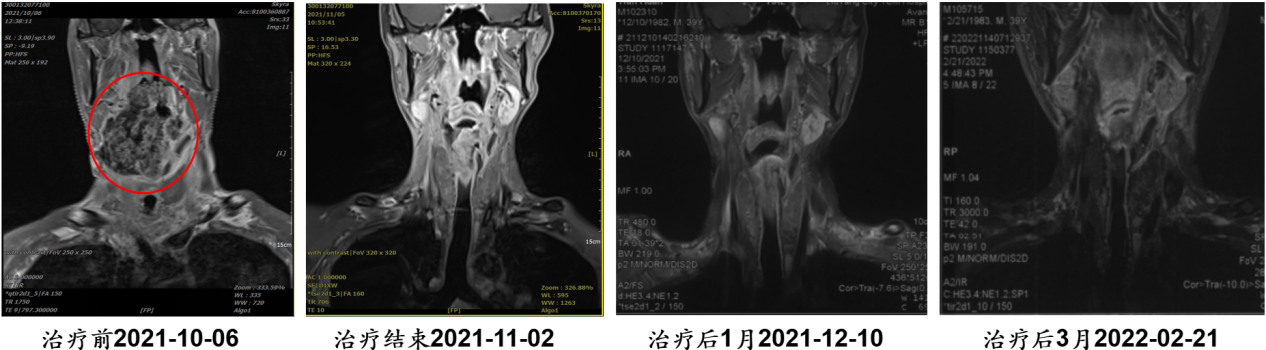

病例7:张某某,男,62岁

· 诊断:腮腺恶性肿瘤,黏液表皮样癌,rT4bN0M0 IVB期

· 难治点:已行两次手术、一次植皮、一次术后放疗,现复发,常规治疗失败

· 重(碳)离子治疗:疗程3周

· 结果:治疗期间肿瘤变化不大,治疗结束出院后肿瘤快速缩小和不断消退

点评:多次复发、多种治疗失败后,重(碳)离子成为最后的希望。

【病例提供医生:潘鑫 科室:放疗中心一科】